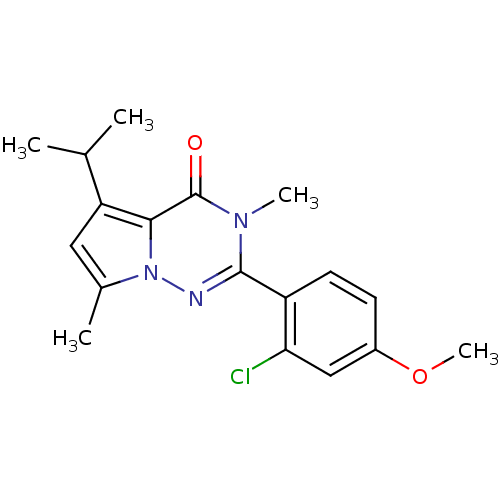

TargetCorticotropin-releasing factor receptor 1(Homo sapiens (Human))

Dupont Pharmaceuticals

Curated by ChEMBL

Dupont Pharmaceuticals

Curated by ChEMBL

Affinity DataEC50: 0.600nMAssay Description:Antagonist activity at human CRF1 receptor expressed in CHO-K1 cells assessed as CRF-stimulated cAMP accumulation by enzyme immunoassayMore data for this Ligand-Target Pair